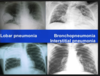

- Identify and discuss diagnostic considerations for evaluating pneumonia.*

- Differentiate between typical and atypical pneumonia

- Typical

- Generally Lobar pattern, classic presentation, “typical” pathogens

- Atypical

- Generally Interstitial pattern, atypical presentation, “atypical” pathogens (no growth on standard culture media, nothing seen on Gram’s stain), Viral